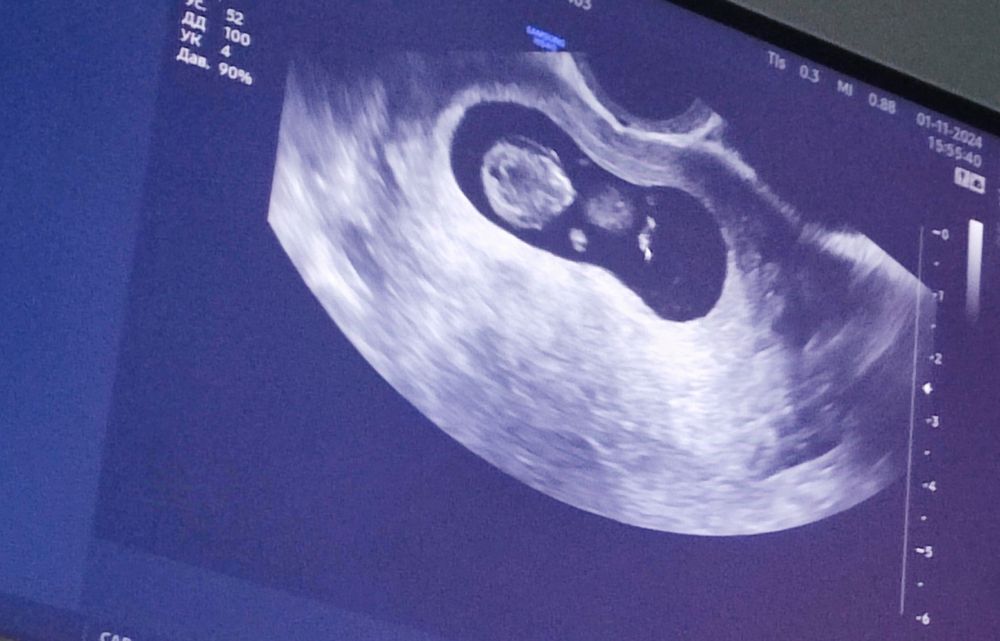

9,5 недель. Узи

В общем, с дитенышем все хорошо, большой такой уже! 3 см;) Пляшет вовсю.

Сердечко бьётся почти 180 ударов, равномерно.

Ручки-ножки, головка, полушария (наверное)) - всё на месте.